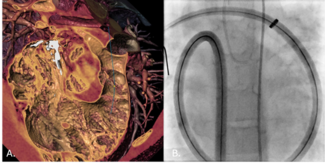

Self-Expanding Aortic Endografts for Endovascular Repair of Native and Recurrent Coarctation of the Aorta

Video Supplement to "Self-Expanding Aortic Endografts for Endovascular Repair of Native and Recurrent Coarctation of the Aorta" (Original Article).